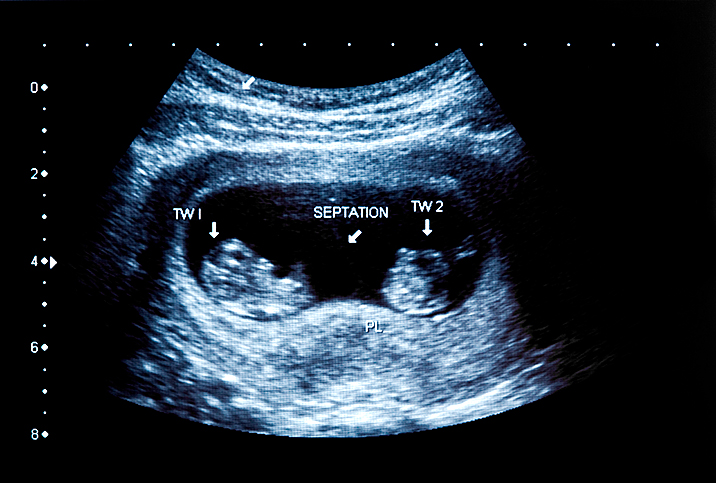

ก่อนหน้านี้ การตรวจรกหลังคลอดใช้เพื่อวินิจฉัยการเสียชีวิตของแฝดหรือแฝดคนใดคนหนึ่งก่อนที่จะหันมาใช้การอัลตราซาวนด์ ณ วันนี้ การตรวจครรภ์ตั้งแต่ช่วงแรกด้วยอัลตราซาวนด์มีใช้กันอย่างแพร่หลายและเข้าถึงได้ไม่ยาก จึงสามารถตรวจจับการมีอยู่ของฝาแฝดหรือทารกในครรภ์ได้ในช่วงครึ่งแรกของการตั้งครรภ์

การตรวจอัลตราซาวนด์สามารถตรวจพบ ‘การหายตัวไป’ ของการตั้งครรภ์แฝด เช่น ผู้หญิงอาจมีอัลตราซาวนด์เมื่อตั้งครรภ์ได้ 6 หรือ 7 สัปดาห์ เมื่อผู้หญิงกลับมาตรวจครั้งต่อไป การตรวจด้วยเครื่องคลื่นเสียงความถี่สูงช่วยให้คุณได้ยินเฉพาะการเต้นของหัวใจเท่านั้น

การทำอัลตราซาวนด์ครั้งที่สองจะมีขึ้นและทำให้ทารกในครรภ์มีความชัดเจนขึ้นเพียงแค่คนเดียว นอกจากนี้ ผู้หญิงบางคนยังมีอาการที่อาจบ่งบอกถึงการแท้ง แม้ว่าจะตรวจอัลตราซาวนด์ได้เพียงเด็กคนเดียวก็ตาม

กลุ่มอาการ Vanishing twin syndrome รับการวินิจฉัยหลายครั้งหลังจากใช้อัลตราซาวนด์ในระยะแรกของการตั้งครรภ์ การคำนวณโดยประมาณแสดงให้เห็นว่าแฝดที่ตายแล้วถูกดูดกลืนหายไปได้ถึง 21-30% ของการตั้งครรภ์แฝด